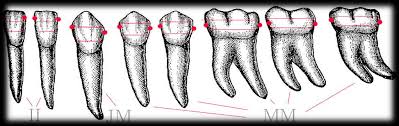

Maradó fogazat

Ideális esetben 32 fogból áll a maradó fogazat. A 32 fogat 4 negyedre (kvadránsra) osztjuk fel, jobb felső és bal felső, valamint bal alsó és jobb alsó. Tehát minden kvadránsban 8 fog található: 3db nagyőrlő, 2db kisőrlő, 1db szemfog és 2db metszőfog.

20 fogból áll a tejfogazat, a szájüreget ekkor is negyedekre (kvadránsokra) osztjuk fel, jobb felső és bal felső, valamint bal alsó és jobb alsó. Minden kvadránsban 5 db tejfog található. Ezek közül 2db tej nagyőrlő, 1db tej szemfog, 2db pedig tej metszőfog.